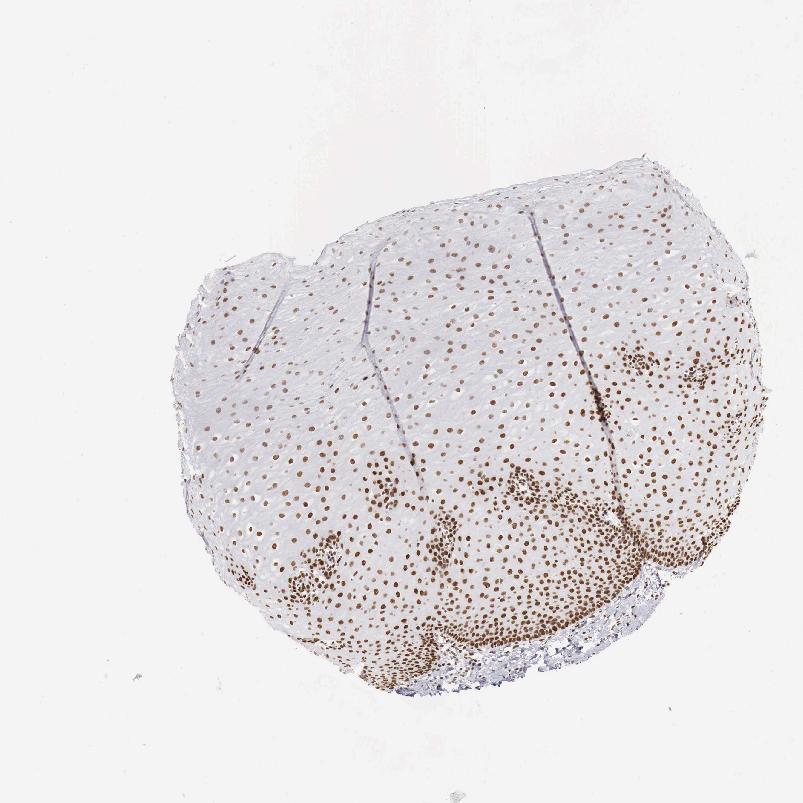

ESOPHAGUS - Antibody stainingi

Antibody staining in the annotated cell types in the current human tissue is reported as not detected, low, medium, or high, based on conventional immunohistochemistry profiling in selected tissues. This score is based on the combination of the staining intensity and fraction of stained cells.

Each image is clickable and will lead to virtual microscopy that enables deeper exploration of all samples and also displays staining intensity scores, fraction scores and subcellular localization as well as patient and tissue information for each sample.

Antibody HPA000538

Squamous epithelial cells High